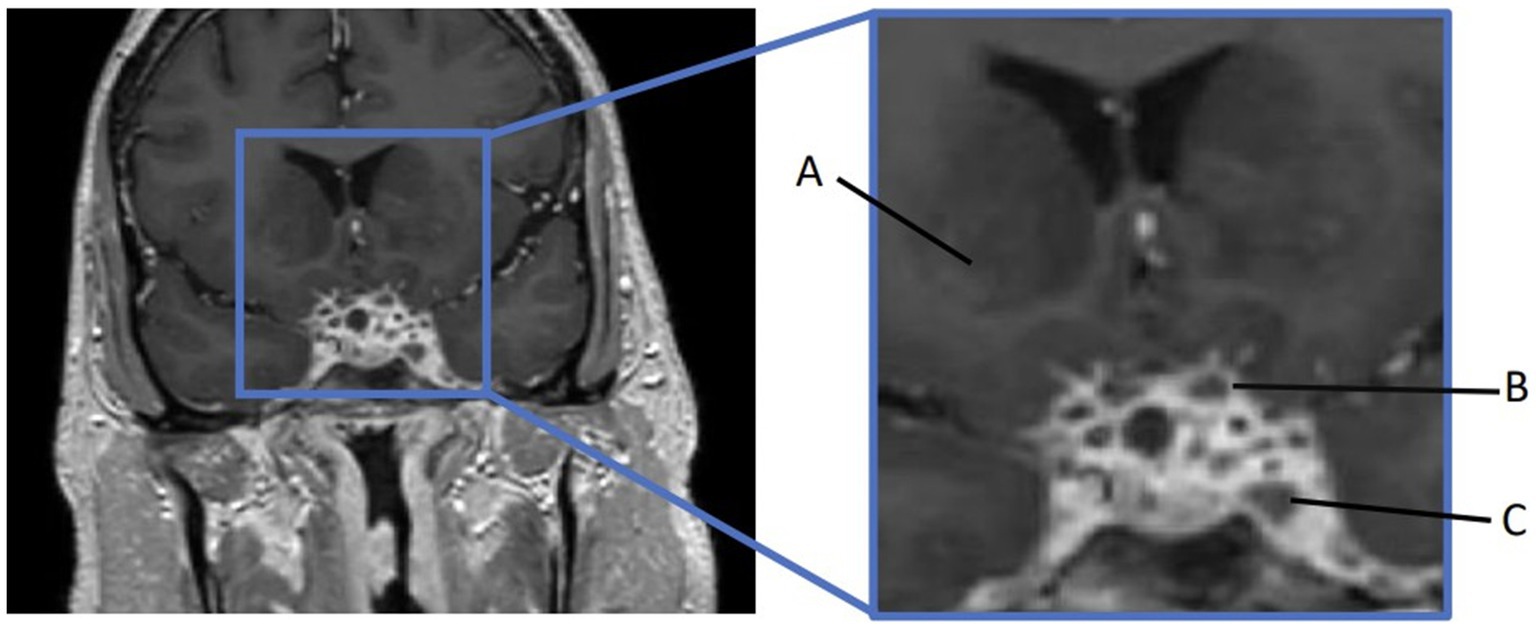

Moreover, 13 weeks after the initial presentation, he returned to the ED with altered mental status and was admitted for evaluation. On examination, he demonstrated word-finding difficulties, impaired attention, and neck stiffness. No other focal signs were noted. MRI re-imaging demonstrated new leptomeningeal enhancement and acute strokes of the bilateral basal ganglia, hypothalamus, and medial temporal lobes, with vascular imaging demonstrating multifocal stenoses with bilateral ICA involvement (Figure 2). The CSF studies revealed significant neutrophilic pleocytosis with an elevated white blood cell count (WBC) of 3,089 uL (72% polymorphonuclear neutrophils (PMNs)), hypoglycorrhachia (35 mg/dL), and elevated protein (124 mg/dL; Table 1). Infectious workup, including bacterial, fungal, and acid-fast cultures; BioFire Meningitis/Encephalitis PCR panel; Nocardia cultures; cryptococcal antigen; and Toxoplasma PCR, was negative. Broad-spectrum antimicrobials, including vancomycin, ceftriaxone, ampicillin, acyclovir, and amphotericin, were initiated for empiric meningitis coverage, covering typical and atypical bacterial, viral, and fungal meningitides in the setting of a seemingly indolent course. Ampicillin and acyclovir were quickly discontinued due to negative testing. The patient was tapered off outpatient steroids during hospitalization. Despite serial CSF studies showing an improving cell count (Table 1), symptoms continued to worsen, leading to a comatose state, which resulted in the patient being intubated and transferred to the intensive care unit on hospital day 3. Serial imaging showed new and expanding regions of diffusion restriction involving the basilar artery territory, as well as proximal posterior cerebral artery stenosis presumably secondary to vasospasm (Figure 3). Magnetic resonance angiography of the head showed enhancement around the basilar artery, raising concern for infectious vasculitis.

Figure 2. At the ED admission with altered mental status, MRI brain demonstrating basal ganglia and medial temporal infarcts. CTA head demonstrating multifocal stenoses involving bilateral ICA.

Figure 3. MRI brain T1 + C when the patient lost corneal and pupillary reflexes. Subsequently transferred to the ICU. (A) Patchy enhancement within basal ganglia. (B) Worsened leptomeningeal enhancement around the suprasellar cistern. (C) Non-enhancing cystic focus suggesting thrombus or abscess.